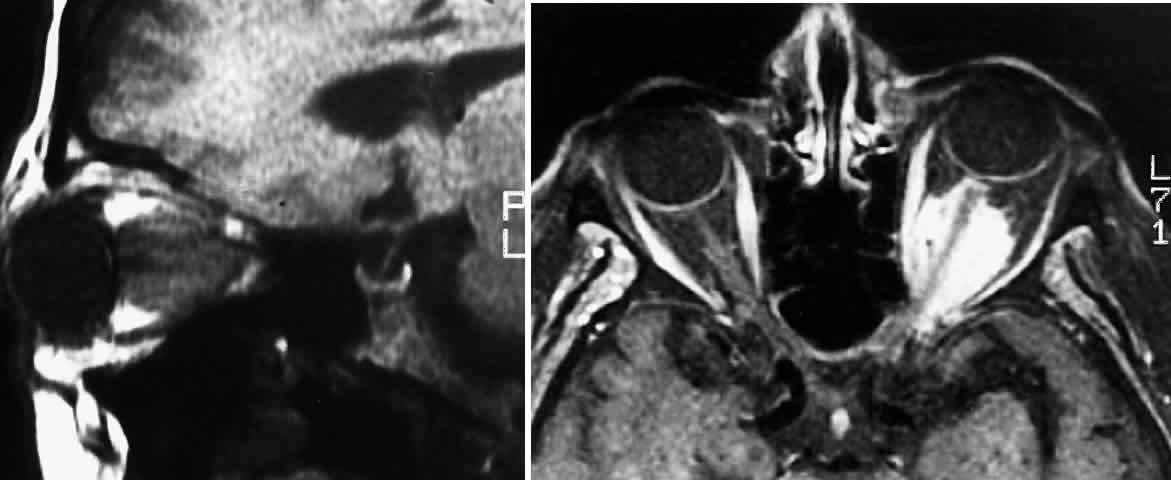

Proptosis is most common in patients with intraorbital tumors, although it can sometimes be observed in patients with concomitant chiasmal and intraorbital involvement3 (Figs. 1 and 2). Proptosis can be the presenting sign in glioma patients, and may even precede visual loss.13 Pain associated with the proptosis is not characteristic of optic gliomas.4 Minimal to severe proptosis, generally nonpulsatile and axial in nature, has been described, but it is typically in the range of 2 to 4 mm. Severe proptosis may jeopardize the health of the globe; it may also be a major cosmetic problem. The tumor itself is usually not palpable. Standardized A-scan examination of optic nerve gliomas demonstrates echograms of regular, homogeneous, low-to-medium reflectivity. On B-scan examination, large optic nerve gliomas appear as fusiform masses replacing the optic nerve void.41 In contrast to optic gliomas, meningiomas are typically irregular in structure and demonstrate higher internal reflectivities.41,42 The 30° test is usually negative when performed on gliomas because of the solid infiltration of the nerve; however, positive tests have been noted, suggesting perioptic subarachnoid fluid surrounding the tumor.42

Fig. 1. Five-month-old infant presenting with progressive proptosis caused by an optic pathway glioma. There is mechanical restriction of the motility of the affected right eye.

Fig. 2. Contrast-enhanced T1-weighted axial MRI of the orbits of the patient in Figure 1, demonstrating a large optic pathway glioma with posterior extension into the optic tracts and radiations. (Courtesy of Orlando Ortiz, MD, and Jeffrey Hogg, MD)

MRI has replaced CT scanning as the optimum test for imaging optic gliomas (Fig. 4 A and B). Optic gliomas have normal to slightly prolonged T1 relaxation times and appear isointense to slightly hypointense to normal brain on T1. Because many of these tumors have prolonged T2 relaxation times, images that are T2 weighted may be used to assess gross tumor margins and posterior extension.72 Optic nerve gliomas often demonstrate minimal enhancement after administration of contrast. To improve MR imaging of optic nerve lesions, a gadopentetate dimeglumine enhancement technique combined with fat suppression can be utilized. Unlike meningiomas, the thickened sheath from arachnoid hyperplasia associated with gliomas will not enhance.77 Although imaging should initially be performed in the axial plane to allow visualization of both the optic nerve and the posterior optic pathways, sagittal views are helpful in demonstrating chiasmal involvement; coronal views can be utilized to delineate intracanalicular tumor.78

Fig. 4. A. T1-weighted sagittal MRI of a patient with neurofibromatosis type 1, demonstrating enlarged optic chiasm consistent with optic glioma. B. T1-weighted coronal image with gadolinium and fat suppression in the same patient, demonstrating the chiasmal glioma.